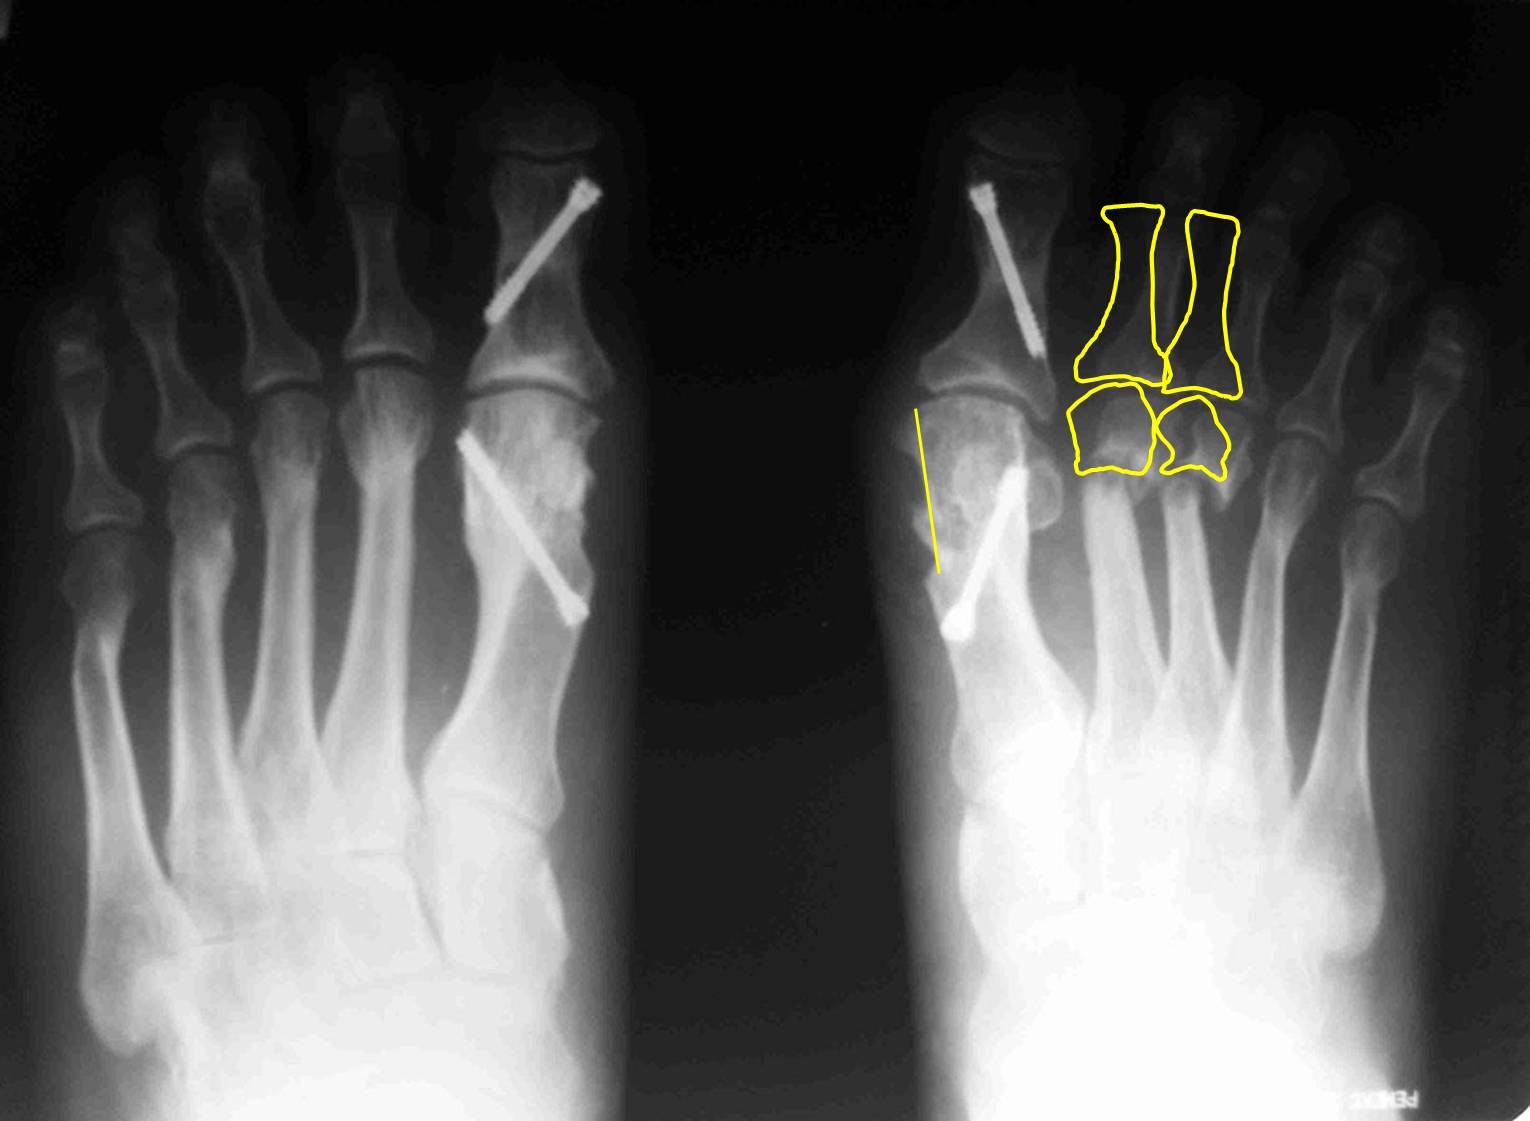

случай.  Из предложенного Вами плана не ясно, зачем делать SERI? Ее ведь

сделали год назад. Только не стандартный вариант с фиксацией спицей, а

более сложный, с внутренней фиксацией. Возможно, в этом была причина

избыточной  латерализации головок: подошвенные пластинки 1 и 2

плюснефаланговых суставов тесно связаны. Слишком радикальное уменьшение

первого межплюсневого угла за счет латерального смещения головки

первой плюсневой привело к дестабилизации нефиксированных остеотомий 2 и

3 плюсневых. И если сейчас еще больше переместить головку первой

плюсневой кнаружи, это только усугубит ситуацию. На схеме я показал, в

каком положении окажутся 2 и 3 пальцы в случае репозиции головок их

плюсневых: расстояния между 1 и 2 лучами итак практически не остается. Я

бы в данном случае подровнял внутренний контур головки 1 плюсневой,

удалил винт из основной фаланги, выполнил латеральный релиз 1

плюснефалангового, эйкиноподобную остеотомию основной фаланги 1 пальца;

репозицию головок 2-3 плюсневых  с фиксацией их головок спицами на 4-6

недель и положив в область ложных суставов костную аутостружку или

какой-нибудь искусственный заменитель кости. Если при этом пальцы не

станут ровнее – выполнил бы остеотомии основных фаланг соответствующих

пальцев. Без вмешательства на 4-5 плюсневых.